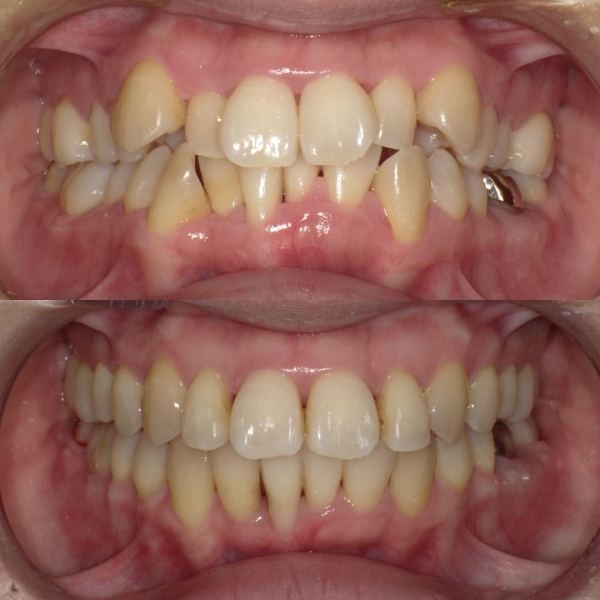

そういった様々な要因を取り除くことで、従来、小臼歯(4番、5番)を抜歯しなければ治療できない症例でも、非抜歯で治療可能となってきているのです。

機能的に小臼歯は非常に大切な歯であることから、最大限小臼歯を抜歯せずに治療できる治療方針を考えます。

また、下顎の位置関係、歯の傾きなどの原因を新素材ゴムメタルワイヤーで治療を行うことでほとんどの症例で小臼歯を抜歯しなくても治療可能になってきています。